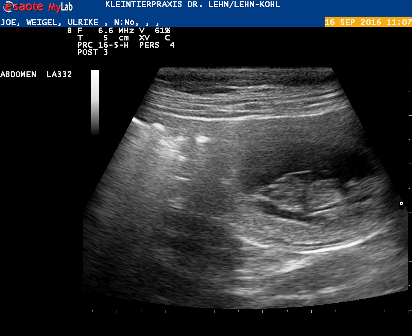

Ihr geht es gut und der Ultraschalltermin steht fest: Freitag, der 16. September

Joe ist trächtig!

Deutlich konnte man die kleinen Joes sehen, wie sie sich bewegten, die Herzchen und die Nabelschnur.

Leider konnten wir nur zwei entdecken :(

Aber jetzt schauen wir erst mal, vielleicht haben sich ja noch ein oder zwei Joes versteckt :)

Und die beiden sind auf jeden Fall da!!